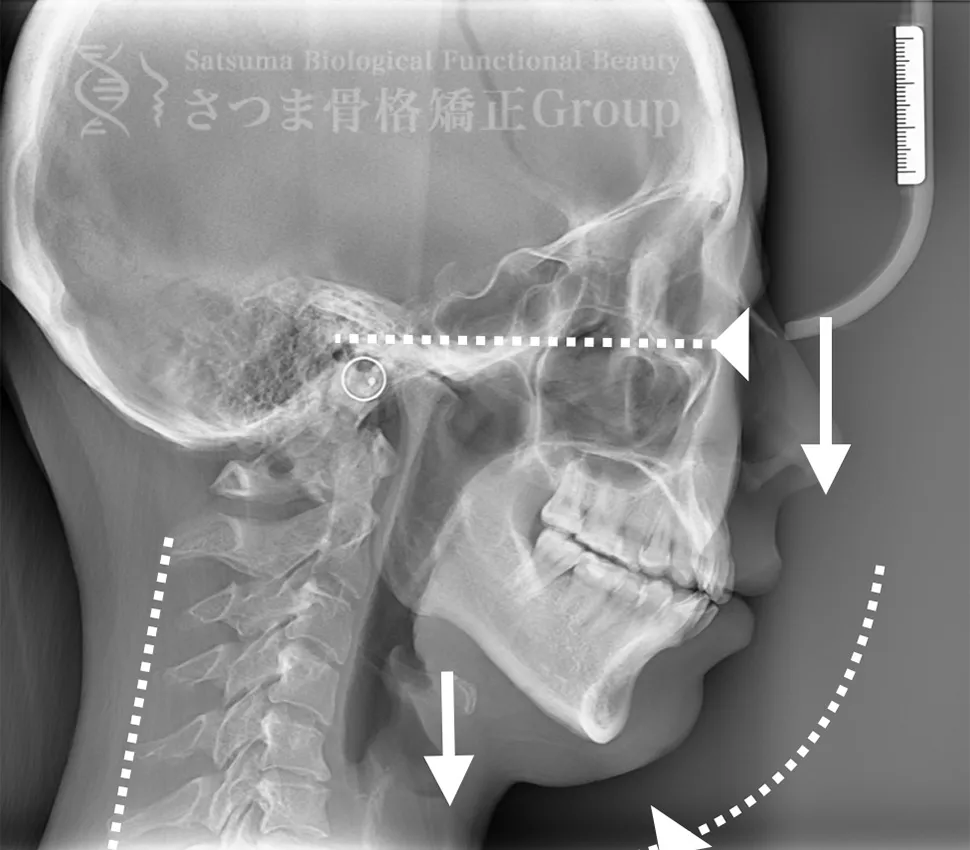

40代男性 F.K様 初回効果

下顎の後方回転あり。 中顔面が伸びて下方に落ちる。 中顔面の奥行きを失っている。 頚椎ストレートネック。 重度の首凝り

Posterior rotation of the mandible The midface is elongated and has dropped downward Loss of depth in the midface Cervical spine straightening (straight neck) Severe neck stiffness

AFTER(マウスピース使用時)

整骨後、形成したマウスピースで形と顎関節の前方回転を誘導。上部頸椎のリリースを促進し、自家矯正力が働きやすいように誘導。蝶形骨口蓋縫合と蝶形骨上顎縫合をモビライゼーションし、可動をブーストし中顔面を短縮。

重度の肩凝りも軽減

After the osteopathy, the custom-formed mouthpiece guides the shape and promotes forward rotation of the temporomandibular joint.

It facilitates the release of the upper cervical spine and encourages the body’s natural self-correcting ability.

Mobilization of the sphenopalatine suture and the sphenomaxillary suture boosts mobility and shortens the midface.